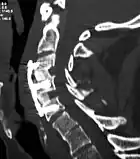

|  X-rays of anterior cervical discectomy and fusion, C5C6 and C6C7. Lateral view. | |

To prevent the vertebrae from collapsing and to increase stability, the open space is often filled with a graft. That can be a bone graft, taken from the pelvis or cadaveric bone; or an artificial implant.[4] The slow process of the bone graft joining the vertebrae together is called "fusion". Sometimes a titanium plate is screwed on the vertebrae or screws are used between the vertebrae to increase stability during fusion, especially when there is more than one disc involved.